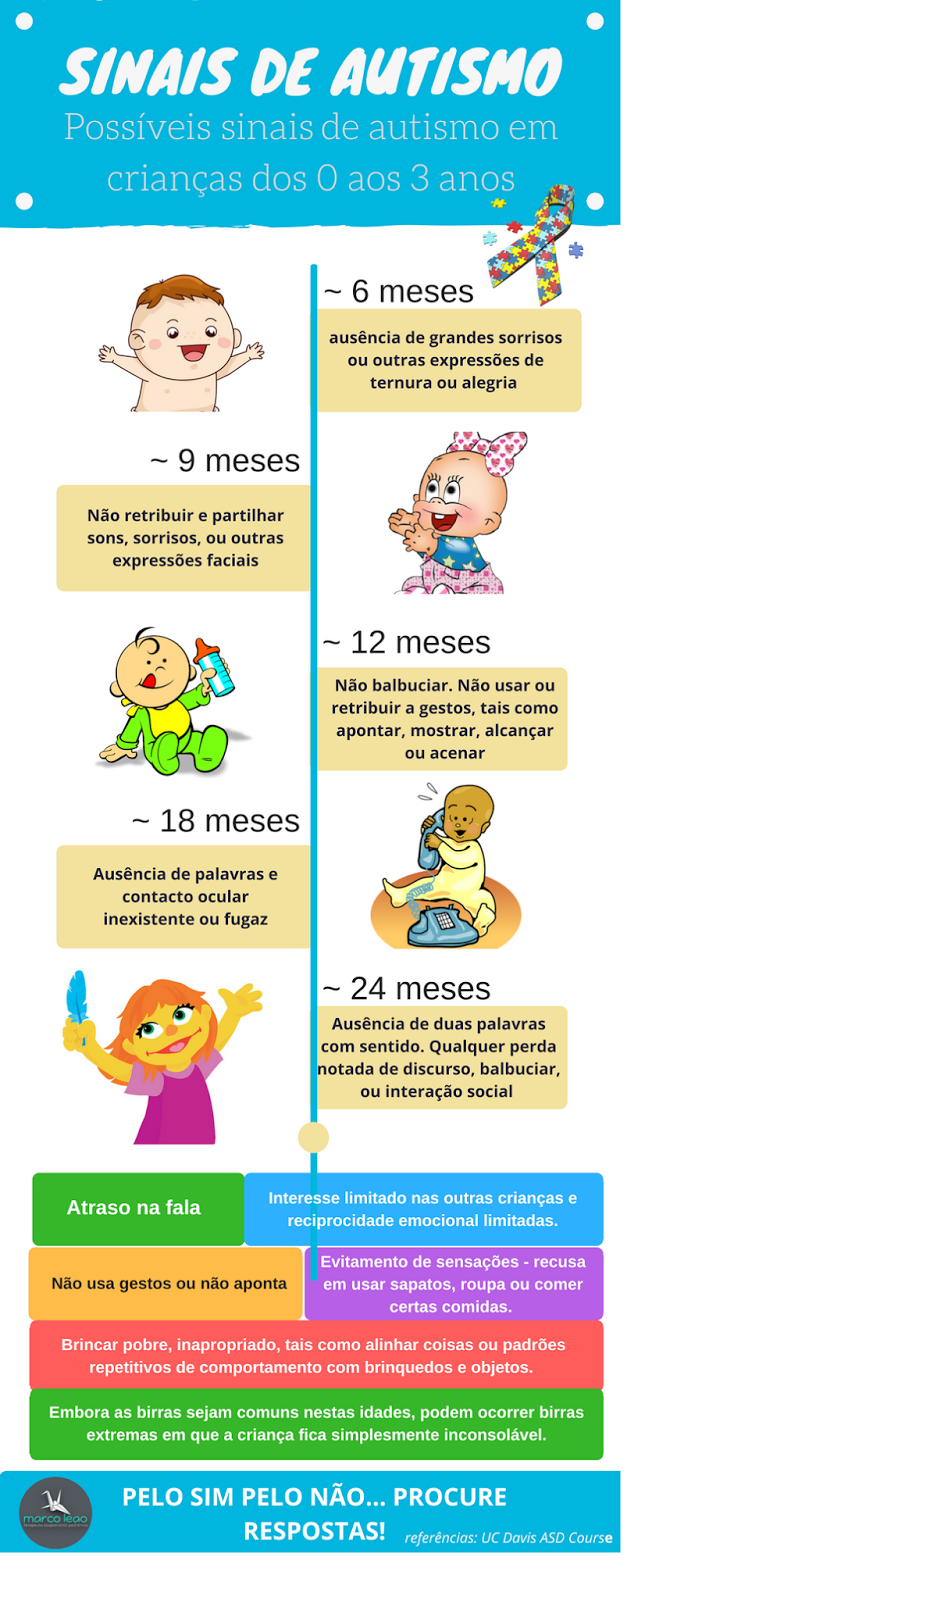

Ainda que haja somente suspeita clínica, quanto mais precoce se inicia o tratamento, maior a qualidade de vida Em geral, a partir de um ano e meio de idade, alguns sinais de autismo — ou Transtorno do Espectro do Autismo, seu nome técnico — já podem aparecer, até mesmo mais cedo em casos mais graves. Há uma grande importância de se iniciar o tratamento o quanto antes, objetivando intervenção terapêutica adequada, mesmo que haja somente uma suspeita clínica, pois quanto antes iniciem-se as intervenções, maior será a qualidade de vida da pessoa. (saiba mais no nosso artigo “O que é

Conheça os primeiros sinais do Autismo! - Blog Rhema Educação04 abril 2025

SelfAzul on X: Veja quais são os primeiros sinais de #autismo em bebês. #infográfico #TEA #luzAzul #selfAzul #autismoerealidade / X04 abril 2025